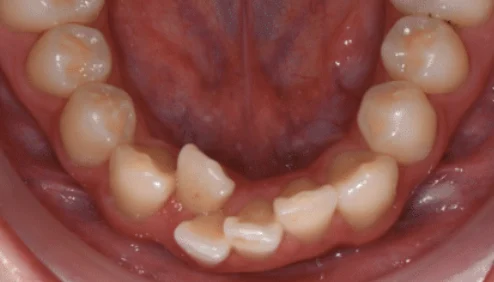

矯正案例-齒列擁擠

Case

案例分享